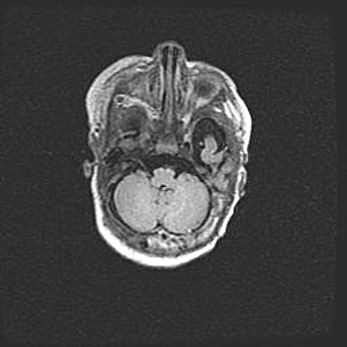

Аномалия Денди-Уокера. Признаки гипоплазии мозолистого тела.

Возраст: 5 месяцев 3 дня

Вес: 5550 г

Пол: мужской

Окружность головы: 39 см

Срок гестации: 40 недель

Аномалия Денди-Уокера – это порок развития головного мозга, для которого характерна триада симптомов: гипотрофия или аплазия червя мозжечка и/или полушарий мозжечка, расширение четвёртого желудочка с формированием ликворной кисты задней черепной ямки, гипертензионная гидроцефалия различной степени.

Гипоплазия мозолистого тела относится к дефектам внутриутробного этапа развития мозговой ткани, возникающим в процессе закладки структур головного мозга, что происходит на начальных этапах развития эмбриона.